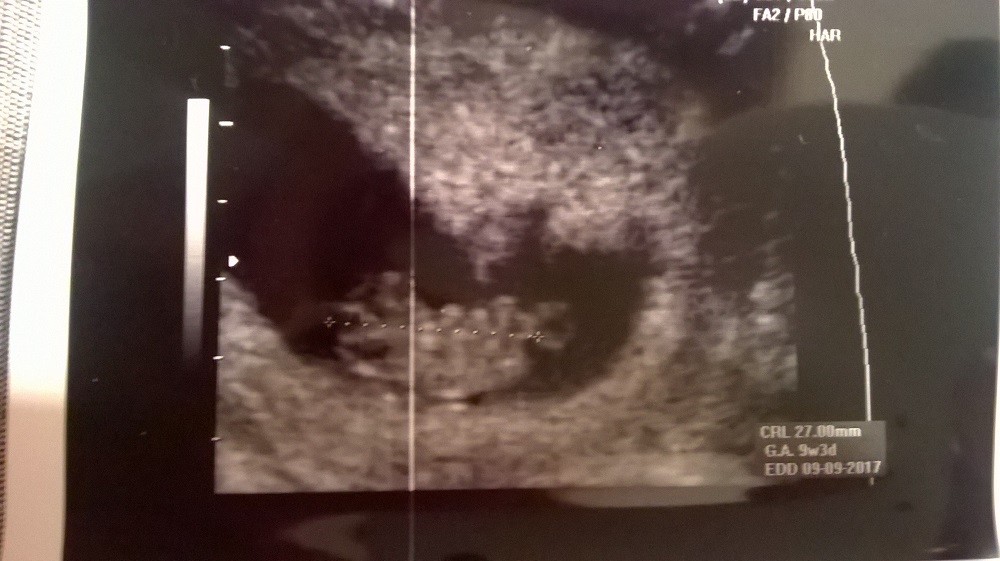

Moje dzidki zdrowe ...:)

WP_20170207_015.jpg

• WP_20170207_015.jpg

174,8 KB · Wyświetleń: 699